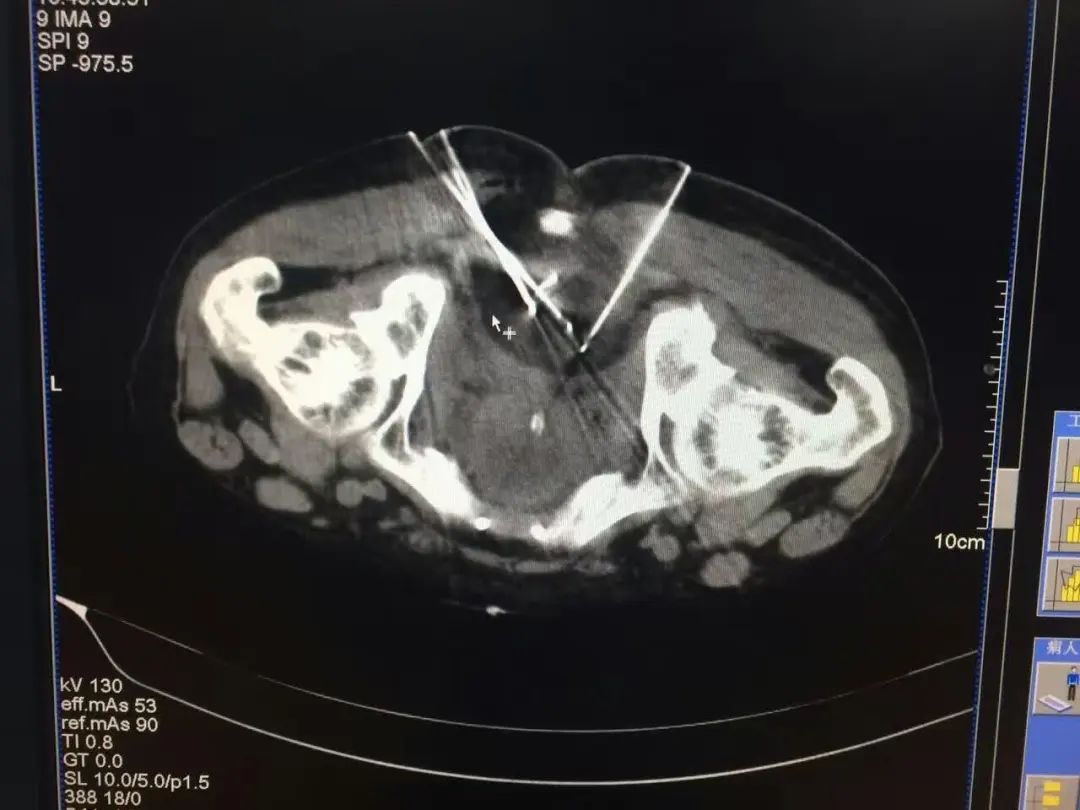

▲该患者为直肠癌术后骶前复发,疼痛难忍,放射性粒子植入是一个很好的挽救性治疗手段。